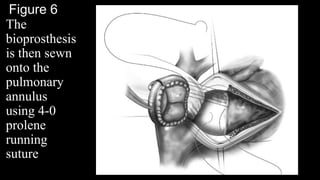

Figure 6

The

bioprosthesis

is then sewn

onto the

pulmonary

annulus

using 4-0

prolene

running

suture

Figure 4 Patch augmentation of

the pulmonary artery. The bovine

pericardial patch is trimmed (A).

The patch is sewn onto the main

artery using 4-0 prolene running

suture (B). In case the patient has

a branch pulmonary stenosis,

patch augmentation is performed

prior to

main pulmonary artery plasty.